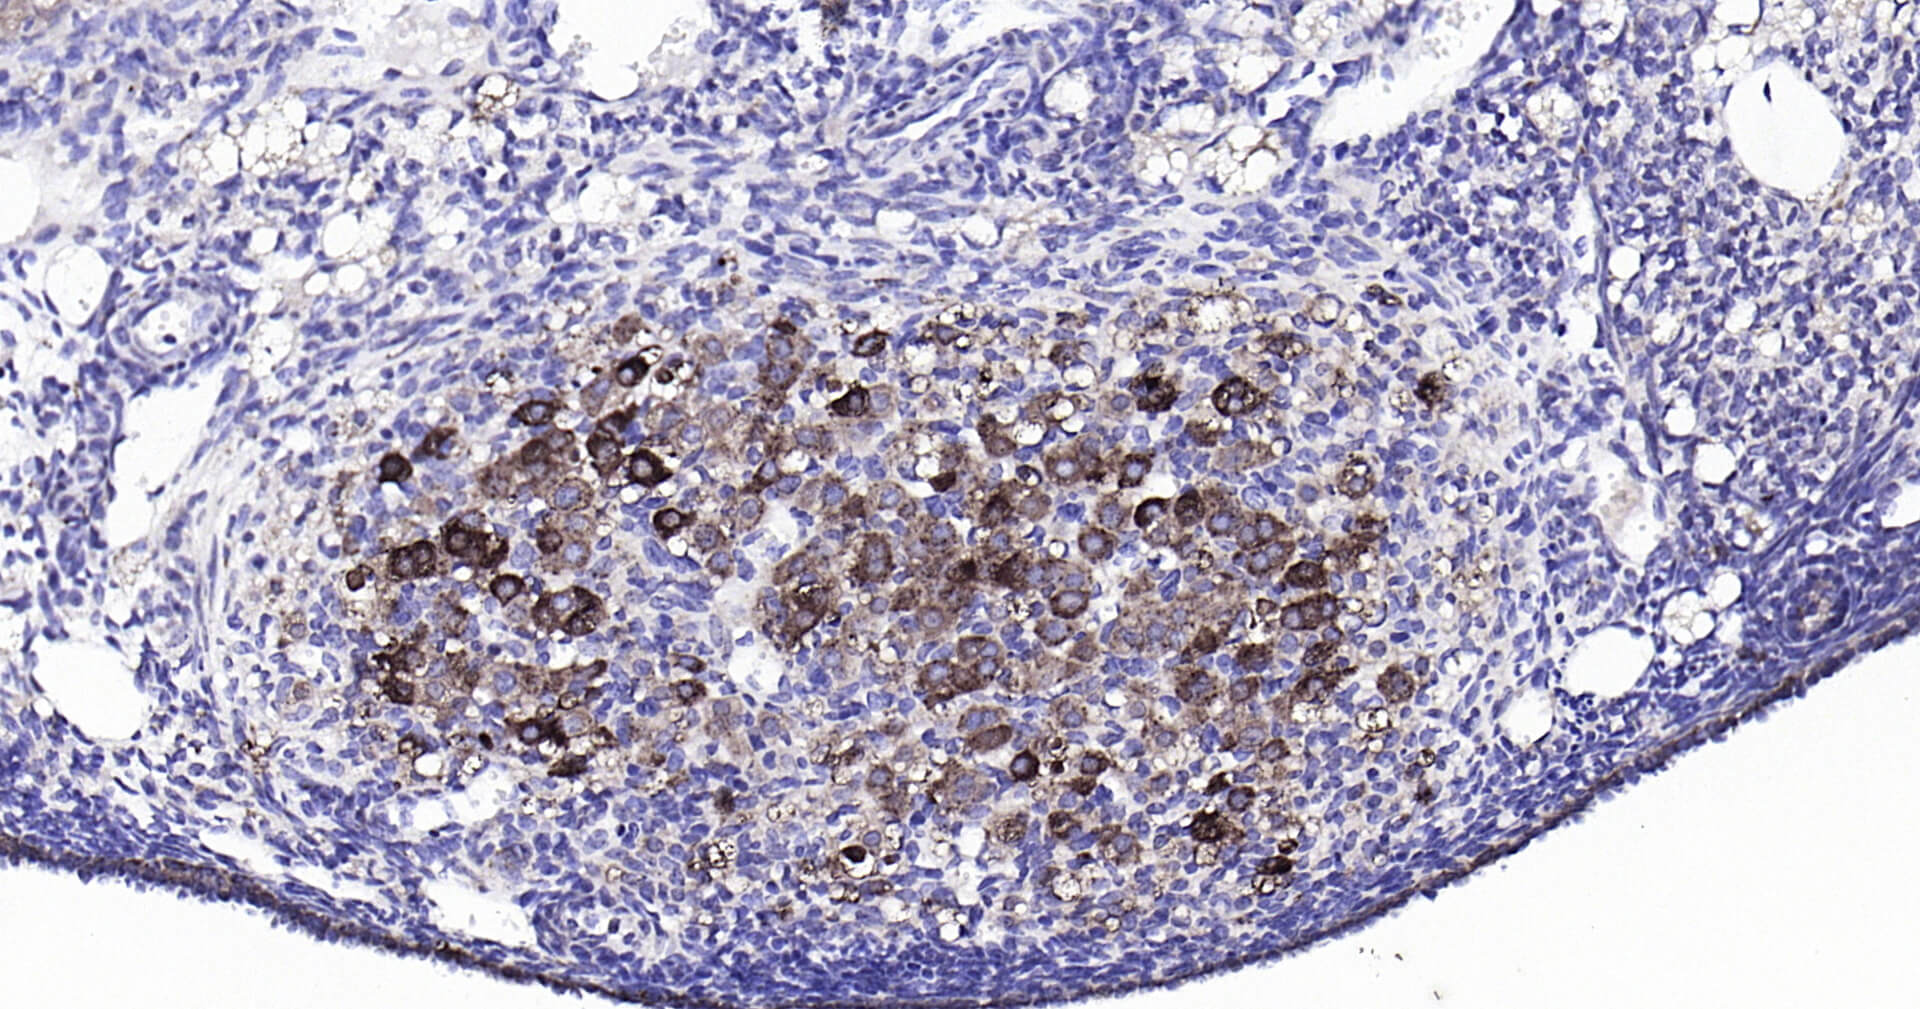

Immunohistochemical analysis of paraffin embedded mouse kidney tissue slide using IHC0124 (Cathepsin L IHC Kit).

Immunohistochemical analysis of paraffin embedded mouse ovary tissue slide using IHC0124 (Cathepsin L IHC Kit).

Immunohistochemical analysis of paraffin embedded rat thymus tissue slide using IHC0124 (Cathepsin L IHC Kit).

Immunohistochemical analysis of paraffin embedded rat kidney tissue slide using IHC0124 (Cathepsin L IHC Kit).